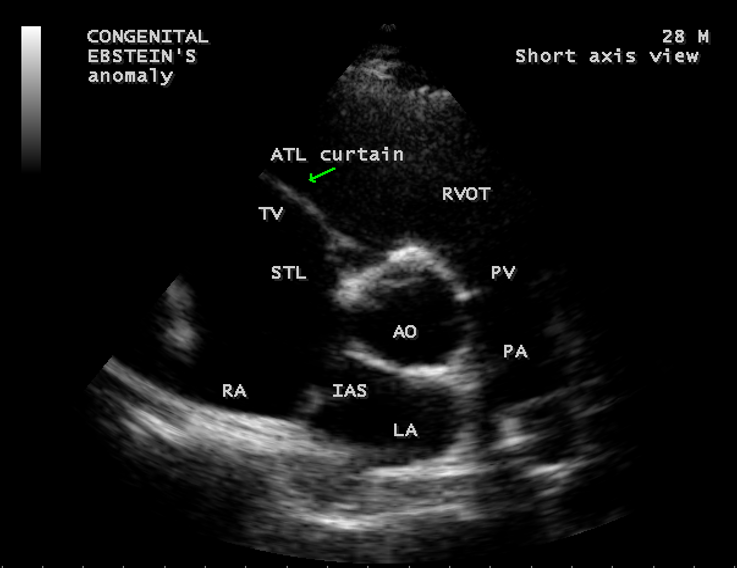

A 28-year old male presented with cyanosis and auscultation revealed a ‘sail sound’ ( loud tricuspid component of first heart sound due to increased tension developed by the large anterior leaflet as it reaches the limits of its systolic excursion- an important sign of anterior leaflet mobility), a ‘cadence’ quality of quadruple rhythm due to wide splitting of first and second sounds ( due to complete right bundle branch block), atrial and ventricular filling sounds (summation of these sounds due to prolonged PR interval). ECG revealed the features of Ebstein’s anomaly as shown in Figures 11 and 12. X-ray chest revealed the Ebstein’s configuration as shown in Figure 13. 2D echocardiography revealed a ‘sail-like’anterior tricuspid leaflet forming a ‘muscular curtain’ in between the inflow and trabecular parts of the right ventricle as an ‘imperforate membrane’ with a ‘pinhole’communication, associated with a muscular VSD (ventricular septal defect) in the proximal, atrialized compartment of right ventricle suggesting an ‘atretic” (‘imperforate’) Ebstein’s anomaly as shown in Figures 14 to 27.

The anterior tricuspid leaflet is not involved in the process of downward displacement, it may be abnormally inserted occasionally and Shiina, et al documented the apical displacement of anterior tricuspid leaflet in 14% of cases echocardiographically [39]. The anterior leaflet forms a large, sail-like intracavitary curtain as in Figures 14, 25 and contains muscular strands instead of consisting entirely of a fibrous membrane as in the normal tricuspid valve [40]. It is potentially mobile with a brisk sail-like movement as shown in Figure 21 to 24 [41], free bloating with a ‘whipping motion’ across the right ventricular outflow tract (RVOT) as shown in Figure 26 and in some cases, the movement is restricted due to its adherence to the ventricular wall as in Figure 1 and 2, 4 and 9. It is often fenestrated, may in part be musculaized , inserting into the trabeculations of the right ventricle (RV) as in Figure 28 and rarely, the anterior leaflet forms an ‘atretic’ membrane that spans the midportion of the right ventricular cavity as in Figure 16.